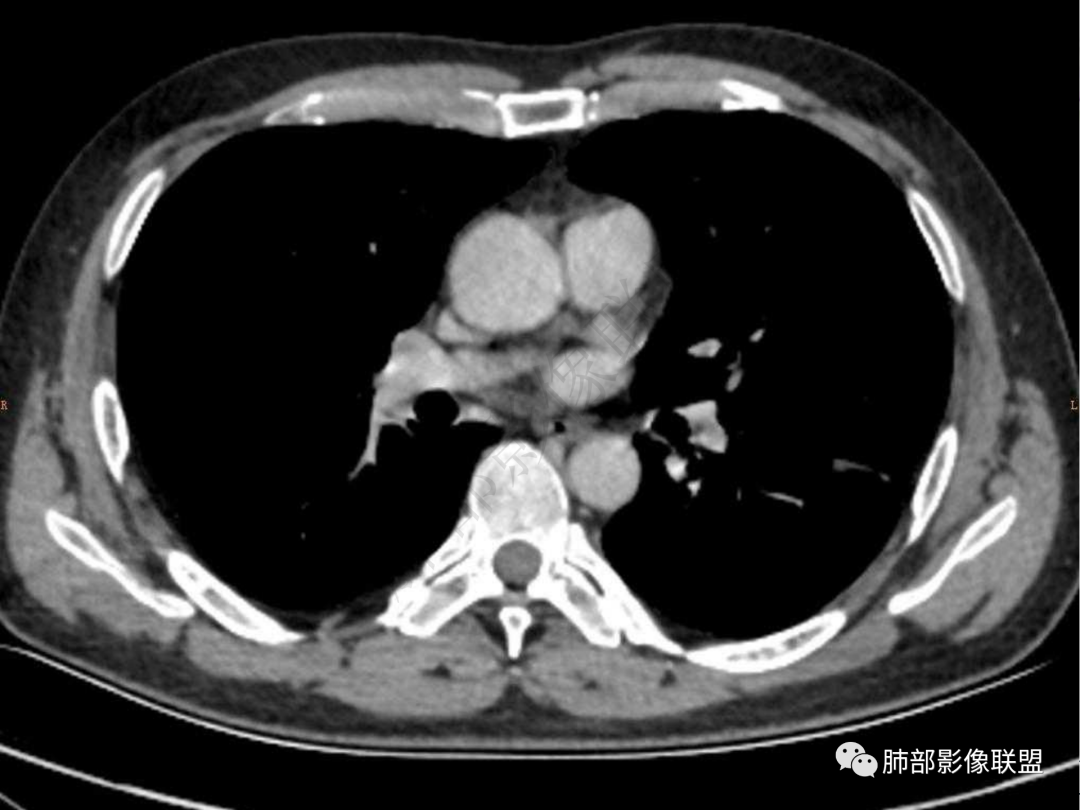

4.实性部分不均匀环形强化并显示一小范围低密度坏死区或空洞。较之肺窗,整体纵隔窗范围较小,提示病灶并不十分密实。抑或为不同时段图像。

肺脓肿:可宽基底与胸膜相连,附近胸膜增厚——炎性特点

肺脓肿:边界模糊不清,或者块影为类圆形,无明显分叶,边缘平直为主,刀切征——炎性特点三、病灶周围特点:肺脓肿:病灶非远端有片状GGO——炎性特点四、近端支气管阻塞:肺脓肿:常有引流支气管伴管壁增厚或者支气管沿洞壁走行。五:坏死壁:肺脓肿:大多壁厚,少数壁薄,没有壁结节,内壁清楚光整——炎性特点

肺脓肿:环形强化,强化较显著。如出现明显囊壁样强化甚至边缘“憩室”样突出,高度支持肺脓肿。